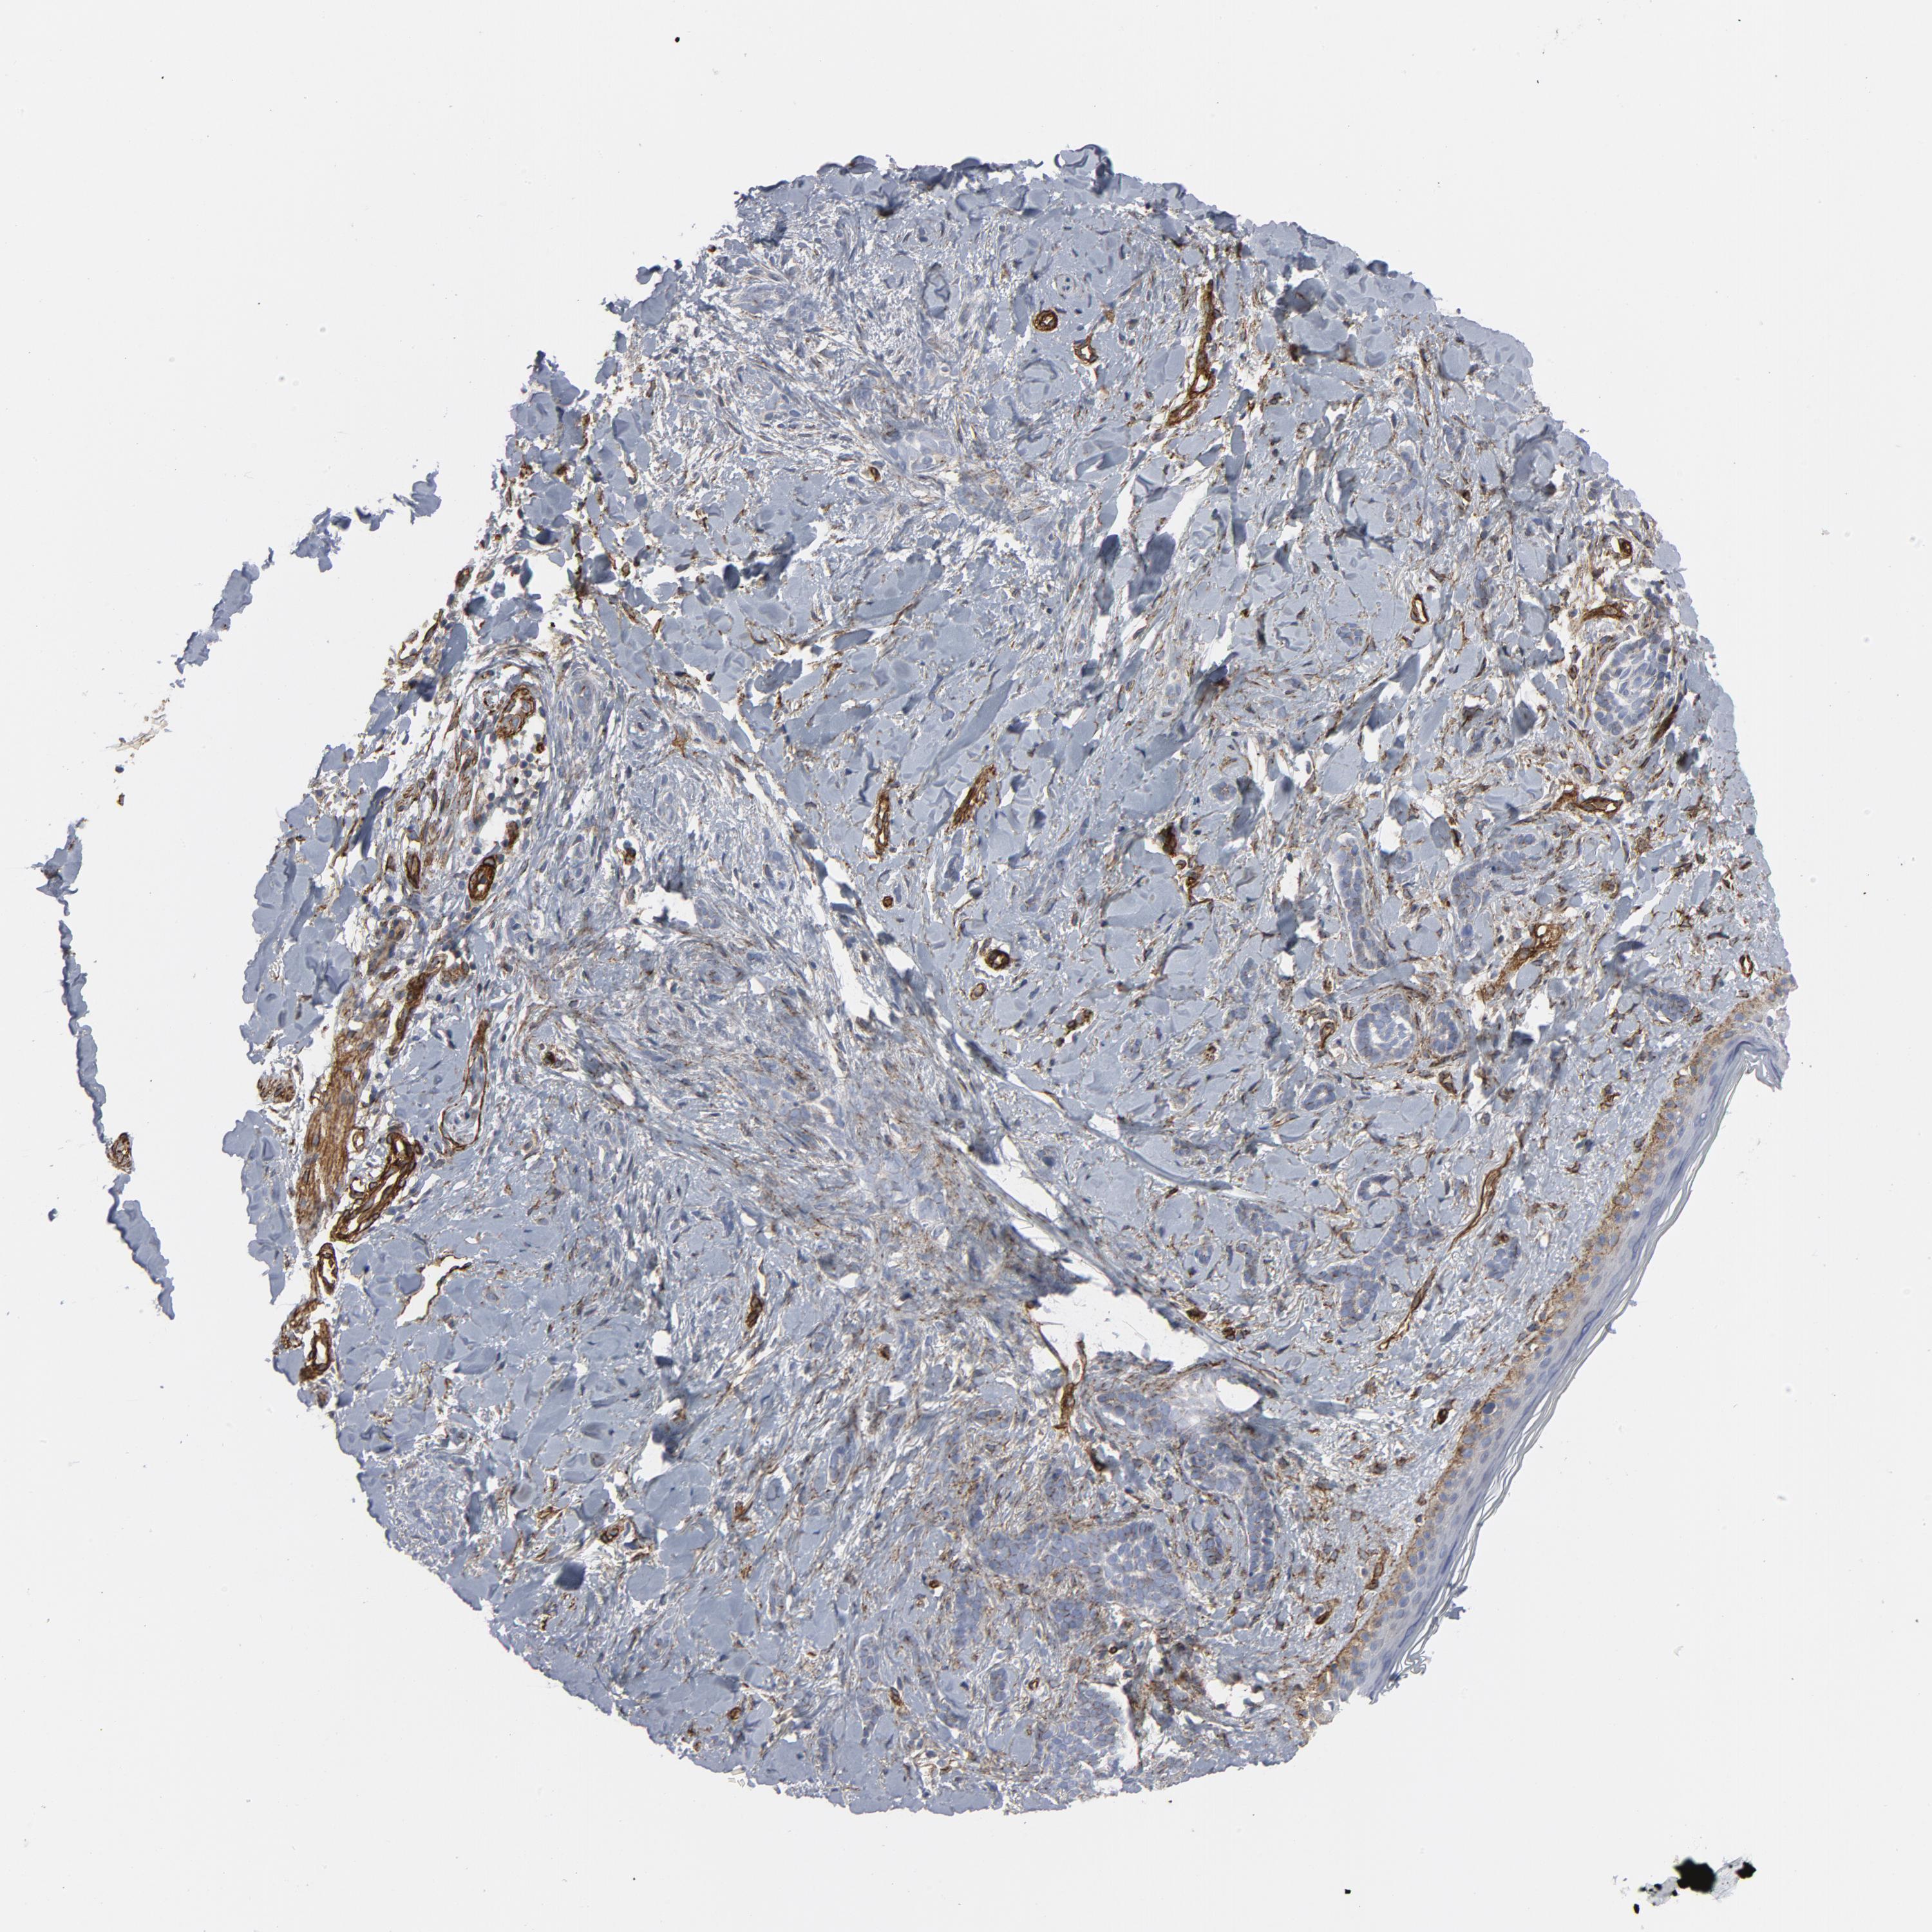

SKIN CANCER - Protein expressioni

A mouse-over function shows sample information and annotation data. Click on an image to view it in a full screen mode. Samples can be filtered based on level of antibody staining by selecting one or several of the following categories: high, medium, low and not detected. The assay and annotation is described here.

Each image is clickable and will lead to virtual microscopy that enables deeper exploration of all samples and also displays staining intensity scores, fraction scores and subcellular localization as well as patient and tissue information for each sample.

Antibody HPA003534

Antibody CAB018380

Staining

High

Medium

Low

Not detected

Intensity

Strong

Moderate

Weak

Negative

Quantity

>75%

75%-25%

<25%

None

Location

Nuclear

Cytoplasmic/membranous

Cytoplasmic/membranous,nuclear

Squamous cell carcinoma, NOS

Basal cell carcinoma

Squamous cell carcinoma in situ, NOS

Squamous cell carcinoma, metastatic, NOS

Adnexal tumor, benign